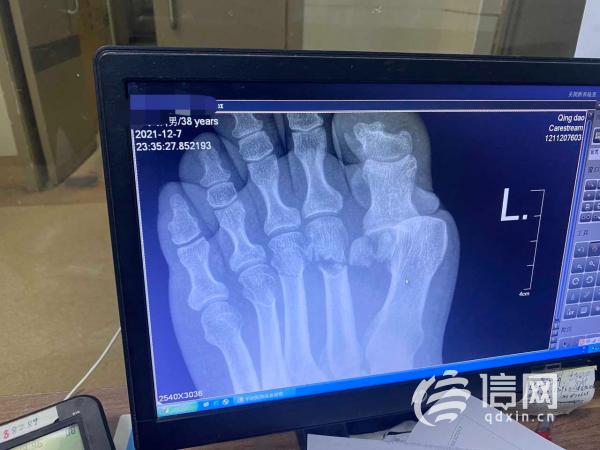

张先生的左脚第2、3跖骨骨折,跖趾关节脱位。 (来源:受访者)

事故发生在2021年12月7日晚上。当时张先生与友人骑摩托车从青岛电视塔下山,驾驶至太平山路S路段时,撞上路边的石墩。因左脚疼痛难忍,他被救护车送往海慈医院。经医院诊断,张先生的左脚第2、3跖骨骨折,跖趾关节脱位,于当晚采用石膏托及支具予以固定。